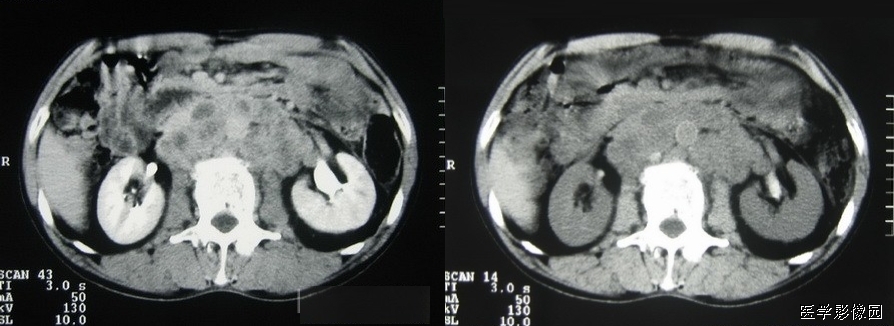

13、三明治征(夹心面包征或夹心饼征)

指2个均质软组织肿物组成三明治面包,系膜脂肪和管状物为构成夹心,是腹部CT横断扫描时的影像表现。系膜脂肪和血管组成夹心,肿大淋巴结组成面包;在给予增强剂后系膜管状结构(血管、肠管)相对脂肪增强,夹心层突出。因为淋巴结增大会压迫血管,阻碍静脉回流,使夹心层内增强的血管更加明显。

当经静脉及口服造影剂后,肠系膜血管结构较脂肪明显强化,从而可使夹心更加突出。导致肠系膜淋巴结肿大的病因很多。除淋巴瘤外,癌、肉瘤、类癌、获得性免疫缺陷相关性淋巴结增生综合征、结核、肠源性脂肪代谢碍及炎症性肠病等也是最常的病因。

三明治征为肠系膜淋巴瘤的特异征象。因为只有在肠系膜淋巴瘤中淋巴结才可以长得很大,并包绕脂肪、肠管和血管而不产生任何临床症状。肠系膜淋巴瘤偶尔可侵犯浆膜及固有肌层,有时会引起小肠出血但极少引起游离性穿孔。肠系膜淋巴瘤还可以引起腹膜后淋巴结肿大。

总之,三明治征指的是CT柏横断面上,巨大增生的肠系膜淋巴结包绕肠系膜脂肪和血管而形成的类似三明治的影像。对于设有移植病史的患者,非霍奇金淋巴瘤是三明治征的主要病因;有移植病史的患者,产生三明治征的原因则可能是淋巴组织增生性疾病,随着接受移植手术的患者不断增多,三明治征可能会在临床上越来越常见。

下图是一个恶性肿瘤腹膜后淋巴结转移患者:

下边两幅图更典型:

图1:非何杰金淋巴瘤患者口服造影剂后增强CT横断面。显示2个巨大系膜淋巴肿物(2个面包-带尾箭头),包绕中心系膜和增强的血管。注意增强的小肠位于周边,腹膜后淋巴结显著增生-箭头)。

图2:患者6个月前曾行左肾移植发现PTLD,血管和口服造影剂横断CT显示三明治征——系膜淋巴肿物(实心带尾箭头),靠近右肾(箭头),有腹膜淋巴结肿大(空心带尾箭头)。